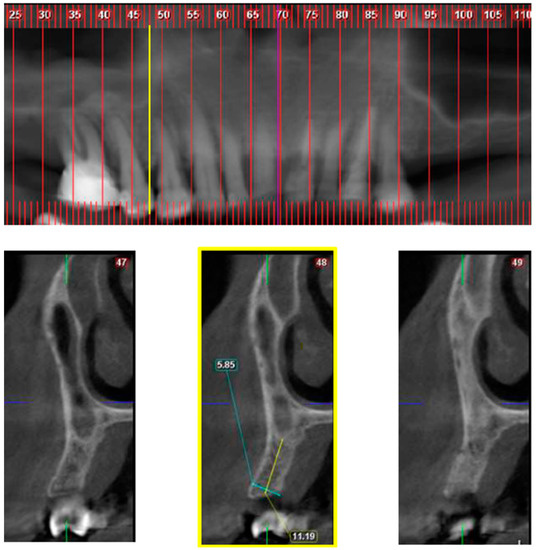

Sinus Augmentation—Expect the Unexpected: Diagnostic Anatomical Study

by Bahaa Haj Yahya, Dror Bar-Hai, David Samehov, Gavriel Chaushu and Yafit Hamzani

“Big-nose variant” is an anatomical phenomenon defined as the pneumatization of inferior third of the nasal cavity within the alveolar ridge while simultaneously displacing the maxillary sinus laterally. The purpose of the present study was to assess the prevalence of the big-nose variant [...] Read more.

“Big-nose variant” is an anatomical phenomenon defined as the pneumatization of inferior third of the nasal cavity within the alveolar ridge while simultaneously displacing the maxillary sinus laterally. The purpose of the present study was to assess the prevalence of the big-nose variant phenomenon and suggest a morphology classification system. Diagnostic anatomical evaluation was performed in a tertiary medical center on 321 randomly selected maxillary cone beam computerized tomography scans of patients who presented at an oral and maxillofacial department. Two anatomical categories were defined for anatomical identification: classes for horizontal mesiodistal distribution, and divisions for vertical distribution. Class 2, defined as location of the nasal/sinus border between the distal edge of the canine up to the distal edge of second premolar, was found to be the most prevalent (64.6%). Class 3, defined as location of the nasal/sinus border distal to mesial edge of the first molar, was found in 17.9% of cases. Regarding the divisions category, in 96% and 58.2% of teeth examined, nasal cavity alone was found to be superior to the canine and first premolar, respectively, defined as Division A. In 46.9% and 85.6% of teeth examined, maxillary sinus alone was located above the second premolar and first molar, respectively, defined as Division C. Identifying Class 3 on the paraxial reconstruction is the first step in identifying big-nose variant, with further assurance gained from each determining division. The use of the classes and divisions may enable better maxillary treatment planning, alert surgeons for the unexpected, and avoid complications. Full article